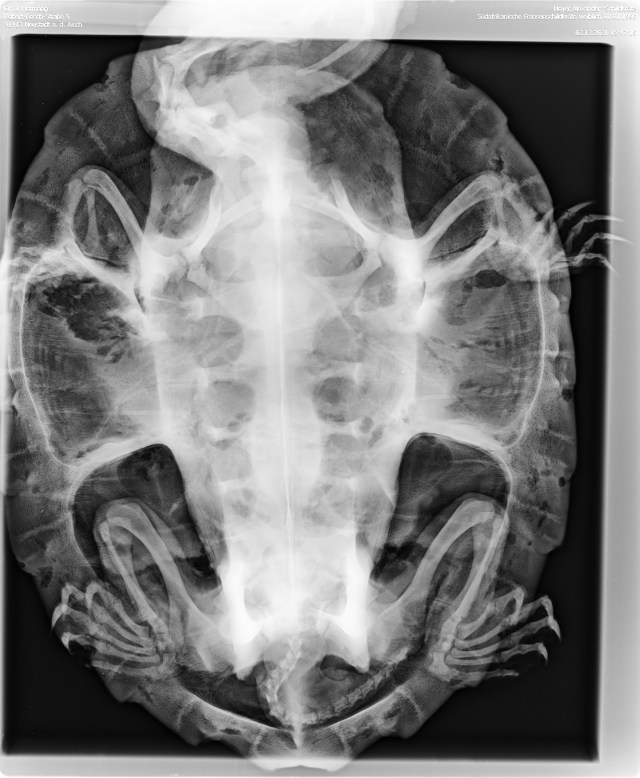

Zur genaueren Beurteilung sollte ich ein Röntgenbild und anschließend einen Kloakenabstrich machen lassen.

Das Röntgenbild zeigte glücklicherweise keine Auffälligkeiten der Lunge.